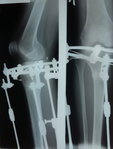

Рентген в 81 день с момента операции.

Здравствуйте, Соломея! По рентгену, у Вас всё отлично! В 90 дней возможно снятие аппаратов. Натаптывайте интенсивно ножки все эти дни, но без фанатизма(ведь когда я Вам говорю больше ходите- это значит, что при физ нагрузке быстрее разрастается костная ткань - вырабатывается, наступает сращение) лучше приехать и остаться у нас в клинике до снятия аппаратов. Один раз можно пожертвовать временем, расстоянием и средствами ради благополучия и отличного результата! Ножки мы исправляем один раз и навсегда!